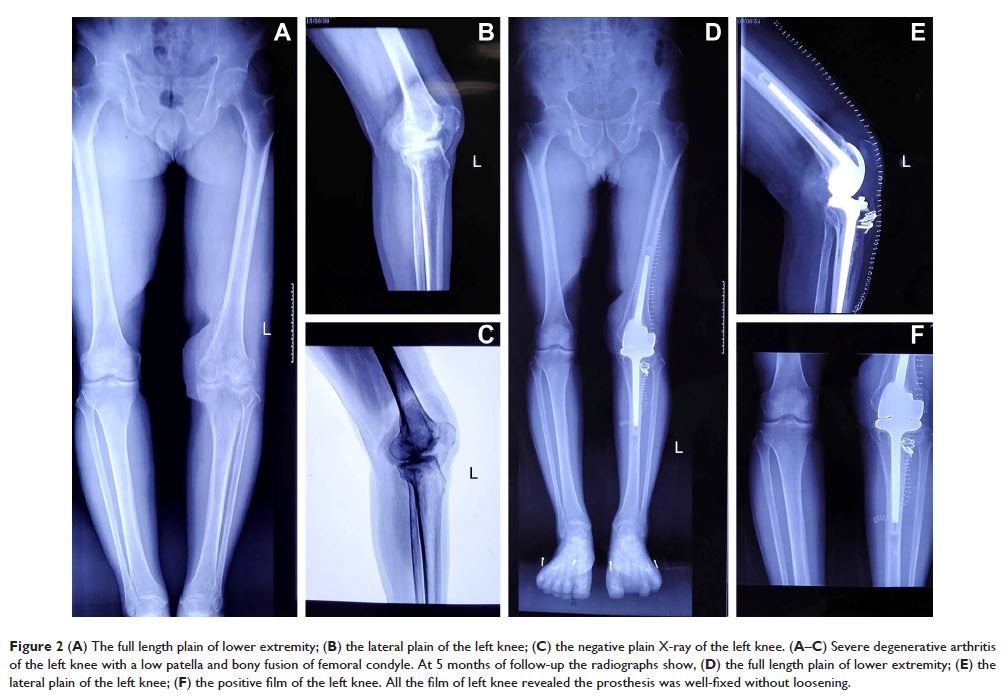

Case Report

- 作者:Yong Xiang, Yi-Yi Xuan, Guangheng Li

- 期刊:Therapeutics and Clinical Risk Management